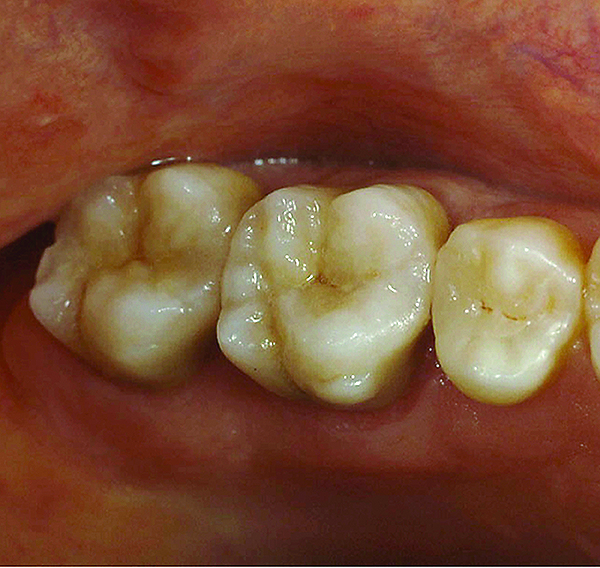

Fig 9. Preoperative view (Fig 9), preparation with composite block-out restoration (Fig 10), and final cementation of CL-IIb material (Fig 11) (final ceramic contour and stain by Steve Lee, CDT, MDC).

Figure 9

Fig 11. Preoperative view (Fig 9), preparation with composite block-out restoration (Fig 10), and final cementation of CL-IIb material (Fig 11) (final ceramic contour and stain by Steve Lee, CDT, MDC).

Figure 11